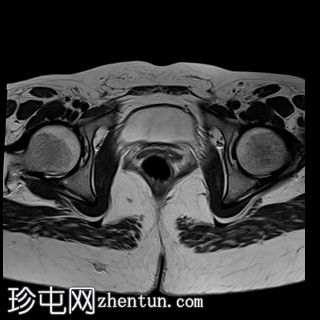

轴位

T2加权像

MRI特征符合剖宫产术后瘢痕子宫内膜异位症,表现为特征性T1高信号伴T1FS持续存在,T2低信号伴内部高信号灶,病灶边缘浸润于腹前壁肌肉内,以及对比增强。

该病灶累及腹白线并浸润腹直肌,主要位于中线左侧,耻骨联合及结节处腹直肌起点上方。

影像学表现符合病灶内出血成分,提示既往剖宫产瘢痕处存在异位子宫内膜组织。

子宫可见剖宫产瘢痕灶。

未见明确的腹膜内或皮下软组织侵犯。

双侧卵巢增大,内含多个小卵泡(每侧卵巢10-12个或更多)。